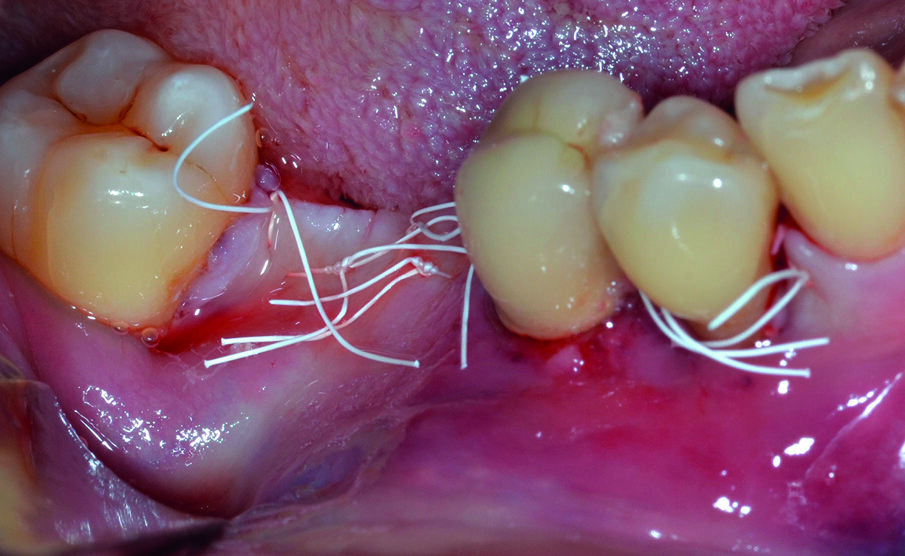

Dopo analgesia locale ottenuta per infiltrazione di Articaina cloridrato 40 mg con epinefrina 1:100.000 viene effettuata l’ incisione di accesso in accordo con il protocollo chirurgico sopra citato (Fig. 4). Al sollevamento del lembo è possibile evidenziare un profondo difetto che coinvolge l’aspetto disto-buccale dell’ elemento 4.5; con una sonda parodontale millimetrata di tipo Williams viene misurata la profondità della componente intraossea (Figg. 5-7). Il debridement della lesione e la decontaminazione della superficie radicolare vengono effettuati mediante una coppia di inserti dedicati montati su dispositivo ad ultrasuoni (ES030LDT ed ES030RDT, Esacrom Srl, Imola, Italia) (Fig. 8).

La chiusura per prima intenzione della ferita chirurgica è affidata a una doppia linea di sutura eseguita con filo in PTFE 4/0, consistente in una serie di punti a materassaio orizzontale intervallati da una seconda linea di sutura a punti staccati, utilizzati anche per chiudere le papille interdentali; poiché a carico dell’elemento 4.5 è presente una mobilità di Grado 2 sec. Miller, al termine della seduta chirurgica lo stesso viene splintato con l’ elemento 4.4 (Figg. 16a-16c).